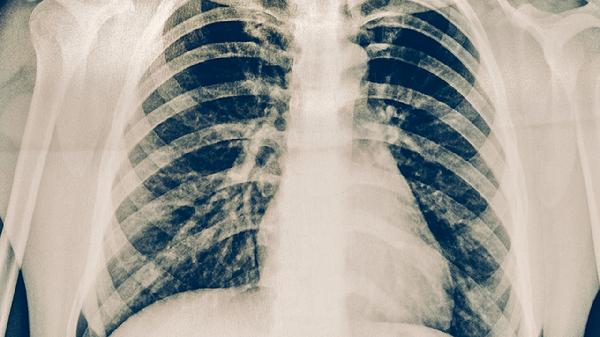

肺结核患者即使症状消失也不应自行停药,痰菌转阴后仍需巩固治疗。标准短程化疗方案通常需要6-9个月,分为强化期和巩固期两个阶段。强化期使用异烟肼片、利福平胶囊、吡嗪酰胺片、乙胺丁醇片四种药物联合治疗,巩固期减少为异烟肼片和利福平胶囊两种药物。治疗期间需定期复查胸部X线、痰涂片及肝肾功能,医生会根据病灶吸收程度、细菌学检查结果调整用药方案。完成全程治疗后,还需进行1-2年随访观察。